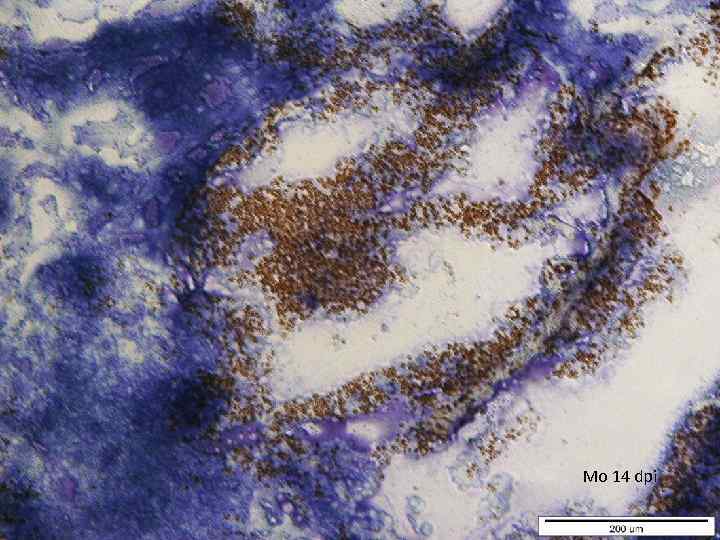

Mo 14 dpi

Mo 14 dpi